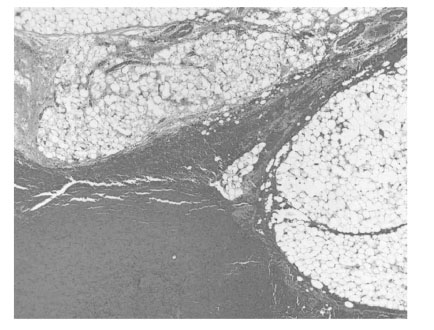

th day of post appendectomy and worsened steadily. On physical examination, asymmetrical swelling without redness on the right groin in the pubic region and mild scrotal swelling were observed with palpable thickened spermatic cord. Neither tenderness or rebound tenderness were noted. Ultrasonography showed an apparent right inguinal hernia containing omental fat (

Fig. 1Ultrasonography showed omental fat containing hernia sac.